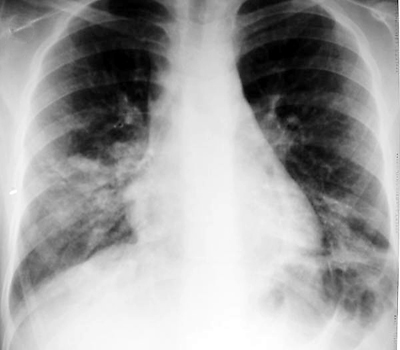

Mycoplasma has a variable presentation on CXR, most commonly presenting as bilateral lower lobe consolidation with small pleural effusions. It may also present with bilateral reticulonodular densities and areas of atelectasis if the infection is predominantly bronchitis.

Example of bilateral lower lobe opacities on CXR in a patient with Mycoplasma pneumoniae.